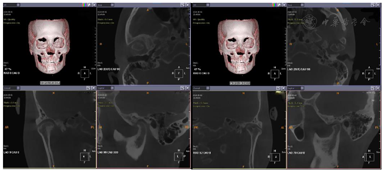

面充填物,未见根充物,根尖无明显异常(图4)。CBCT示:双侧髁突形态不对称,左侧髁突表面中央凹陷,余骨质未见异常(图5)。

影像学检查:曲面断层片及CBCT示,上下颌骨可见多个钛板内固定,12、24、34、44牙缺失。余骨质未见确切异常改变(图12,图13)。